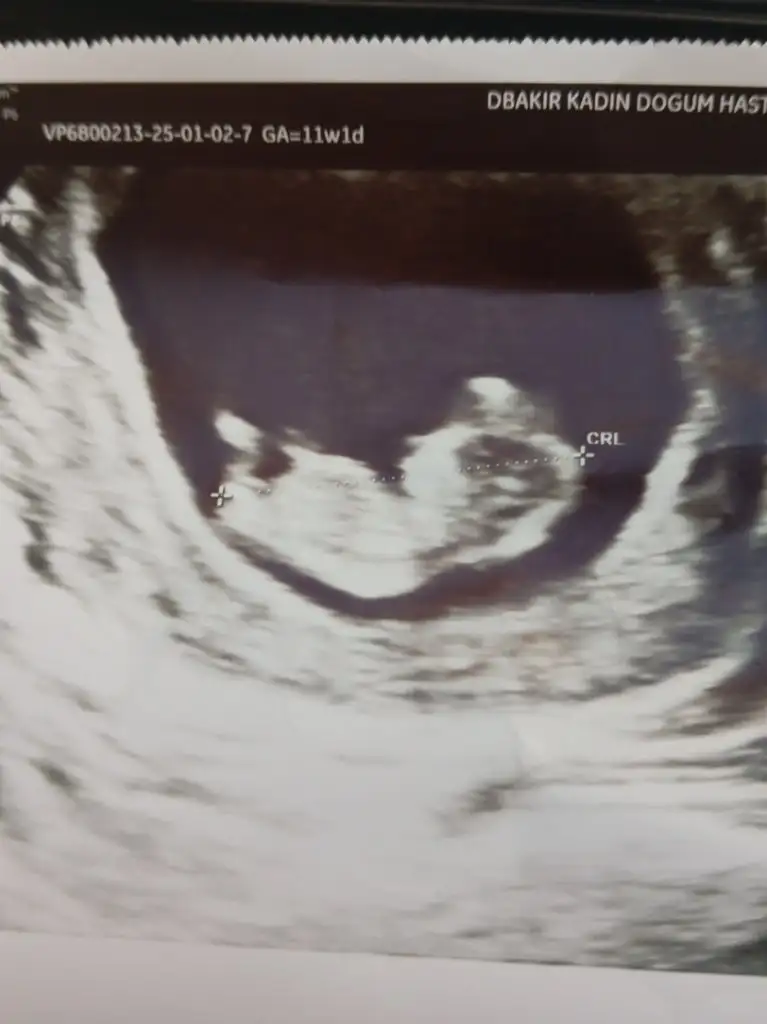

Güzel anneler anne adayları öncelikle inşallah hepinizle sağlıkla bebeklerinizi kucağınıza alırsınız inşallah çocuğu olanlarda Allah uzun ömürler versin... Şimdi sizlerden ricam cinsiyeten anlayan varsa benim bebisime bir tahminde bulunabilir misinz 11 haftalık buarada ☺️ şimdiden çok teşekkür ederim